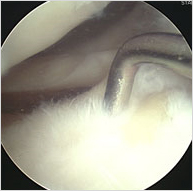

관절내시경은 치료 목적뿐 아니라 진단 목적으로도 사용 할 수 있습니다.치료 목적은 전문 진료 센터의 관절내시경 편을 참조 하여 주십시오.진단적 관절경도 크게 두 가지 용도로 나누어 생각 해 볼 수 있습니다. 우선 일차적 진단 목적입니다. 무릎의 통증이나 외상 시 기본 방사선 촬영 후 특별한 문제가 발견 안되면 바로 진단을 위한 목적으로 관절경을 이용하는 것입니다. 연골이나 인대 손상, 초기 관절염등은 단순 방사선상 나타나지 않기 때문에 카메라를 넣어 의사가 직접 관절 안을 들여다봄으로써 보다 정확하고 많은 정보를 얻을 수 있습니다. 하지만 주의를 요하는 경우도 있습니다. 예를 들어 심한 외상으로 관절낭이 파열되어 있으면 관절경시 관절내로 주입하는 식염수가 파열된 관절낭을 통하여 종아리 근육쪽으로 흘러 심한 부종을 일으킬 수도 있고 많은 시간을 할애 하지 못하고 중단해야 하는 경우도 가끔 발생 합니다. 이런 경우는 MRI를 먼저 촬영 하여 치료 계획을 세우고 치료 목적으로 사용하는 것이 좋겠습니다.

두 번째 진단 목적으로 사용은 , 단순 방사선외에 초음파, MRI, CT 등 필요한 검사를 하였는데도 뚜렷한 병변은 찾을 수 없고 환자는 계속 통증이나 불편감을 호소 하는 경우나 검사상 보이는 이상 소견과 환자분의 증상이 일치 하지 않는 경우 등입니다. 무릎 관절등에 MRI 검사가 상당히 정확한 진단 기기임에도 불구하고 100% 완벽한 것은 아니어서 때로는 MRI 등 다른검사에 나타나지 않는 병변이 관절경을 통해서 발견되는 경우도 있습니다. 관절 질환에서 MRI 가 정확한지 관절경이 정확한지 질문하시는 환자분들이 종종 있습니다. 물론 제일 중요한 진단의 첫 걸음은 환자분의 설명과 의사의 직접 진찰입니다. 이 과정을 통해 필요에 따라 여러 가지 검사 항목이 결정되기 때문에 어떤 추정 진단을 염두에 두었느냐에 따라 사용 용도나 중요성 비중이 조금은 다를 수 있습니다. 예를 들어 류마티스 관절절염은 증상과 X-ray, 그리고 혈액 검사가 진단을 위한 중요부분이고 다른 검사는 치료를 위한 목적으로 추가 할 수 있는 정도입니다.

결론적으로 MRI 와 관절경은 모두 우수한 진단 기기로 어느 쪽이 정확하다기 보다는 서로 보완적이라고 보는 것이 좋겠습니다. 앞서 말씀드린 것과 같이 MRI 에서도 볼 수 없었던 병변을 관절경을 통해 확인 할 수도 있고 또 연골 낭종, 연골판 실질부 손상 등 관절경을 통해서 관찰하기 어려운 부분을 초음파나 MRI를 통해서 확인 할 수 있습니다. 내과에서 사용하는 위, 대장 내시경은 입과 항문을 통해 검사하기 때문에 전혀 절개가 필요 없어 순순한 검사로 이해하시지만 정형외과용 관절경은 관절에 아주 작지만 절개가 필요하여 검사보다는 일종의 수술 개념으로 생각하고 부담을 느끼지는 분들도 많고 국소 마취로 진단이 이루어진 후 수술이 필요하면 다시 절개를 해야 한다는 점에서 불편을 호소하시기도 합니다. 따라서 관절내시경을 진단 목적으로 이용하실 때는 그 목적과 방법을 전문의와 충분히 상의하시고 결정 하시는 것이 좋겠습니다.